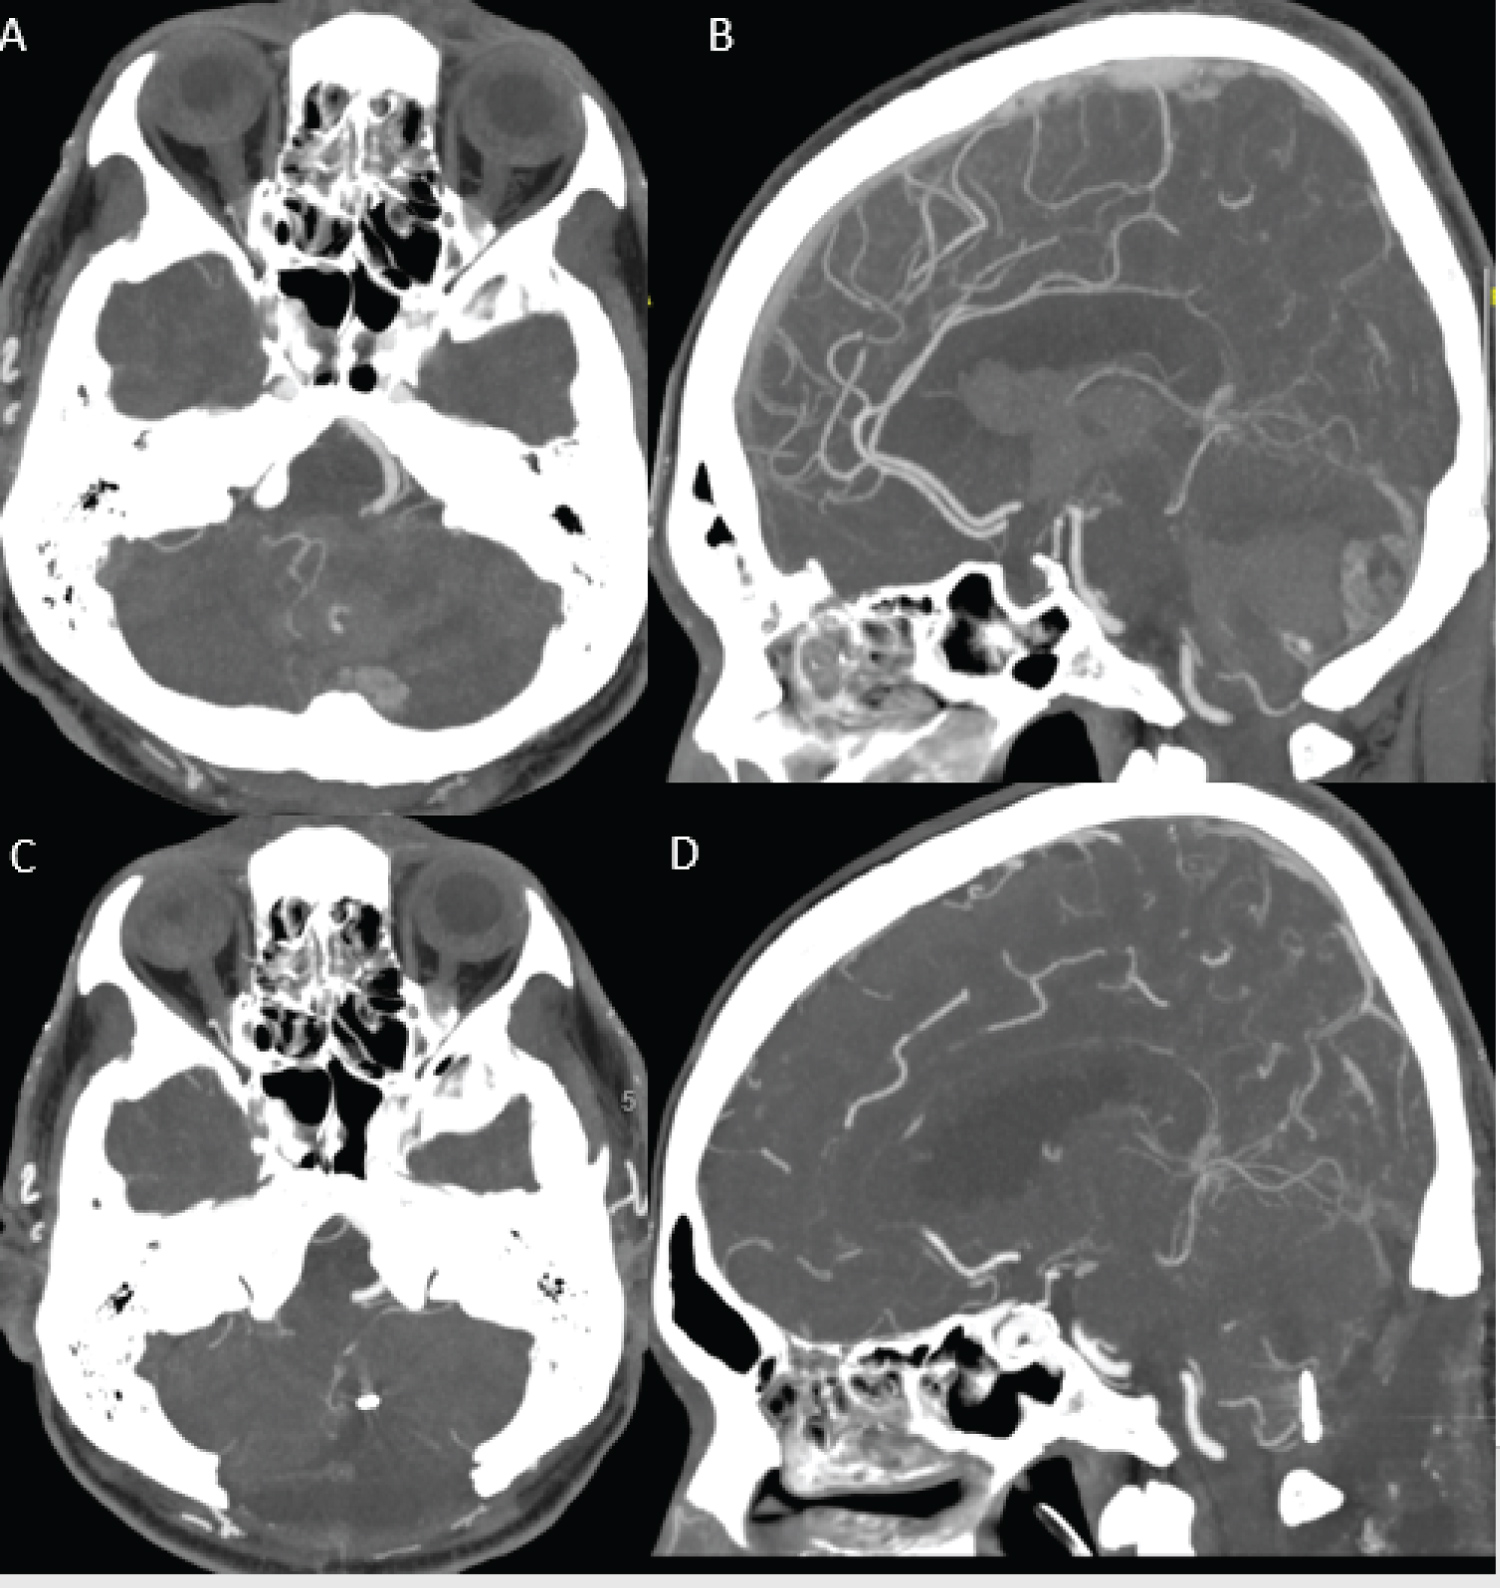

This is a 60-years-old man who developed sudden onset headache and giddiness during his sexual intercourse. He was brought to our hospital with GCS of E2V2M5 on arrival. CT brain was performed and it showed a left cerebellar hematoma with extension into forth ventricle and gross intraventricular hematoma (IVH) as shown in Figure 1. CT angiogram showed a contrast enhancing cystic mass at left cerebellar hemisphere with aneurysm arising from left cortical segment of posterior inferior cerebellar artery (PICA) as shown in Figure 2.

Figure 1: CT angiogram (A and B) Showed left cerebellar ring enhancing cystic lesion with PICA feeder. A flow related aneurysm is noted from cortical branch of left PICA; (C) Subsequent post-op scan showed aneurysm clipped on axial; (D) Sagittal view. View Figure 1